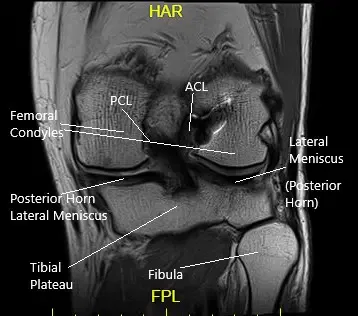

Anterior Cruciate Ligament (ACL)

The ACL runs from the front and middle of the tibia to the outer and backward side of the femur. The ligament provides stability mainly in the front and back of the knee. The ligament also stabilizes the rotatory movement of the knee.

Posterior Cruciate Ligament (PCL)

The PCL is present behind the knee joint. Along with ACL, it provides stability in the front and back of the knee. Similar to ACL, the PCL also provides rotational stability.

Medial & Lateral Collateral Ligaments

The medial collateral ligament provides stability on the inner side of the knee. Similarly, the lateral collateral ligament provides stability on the outer side of the knee.